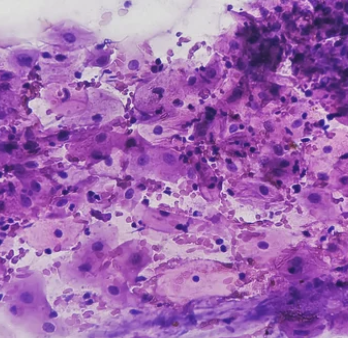

3. 조직 검사

- 자궁경부 세포검사나 HPV 검사에서 이상이 발견되면 조직 검사를 통해 자궁경부의 세포 조직을 직접 채취하여 더 정확한 분석을 진행합니다. 이를 통해 암세포의 유무와 진행 정도를 진단할 수 있습니다.